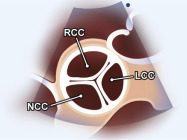

|

||||||||

|

|

Cửa sổ siêu âm cạnh ức

Mặt cắt trục ngắn cạnh ức Phóng đại hình ảnh van động mạch chủ để đánh giá các lá van |

Lá không vành (LCC) Lá vành phải (RCC) Lá vành trái (LCC) |

|||||